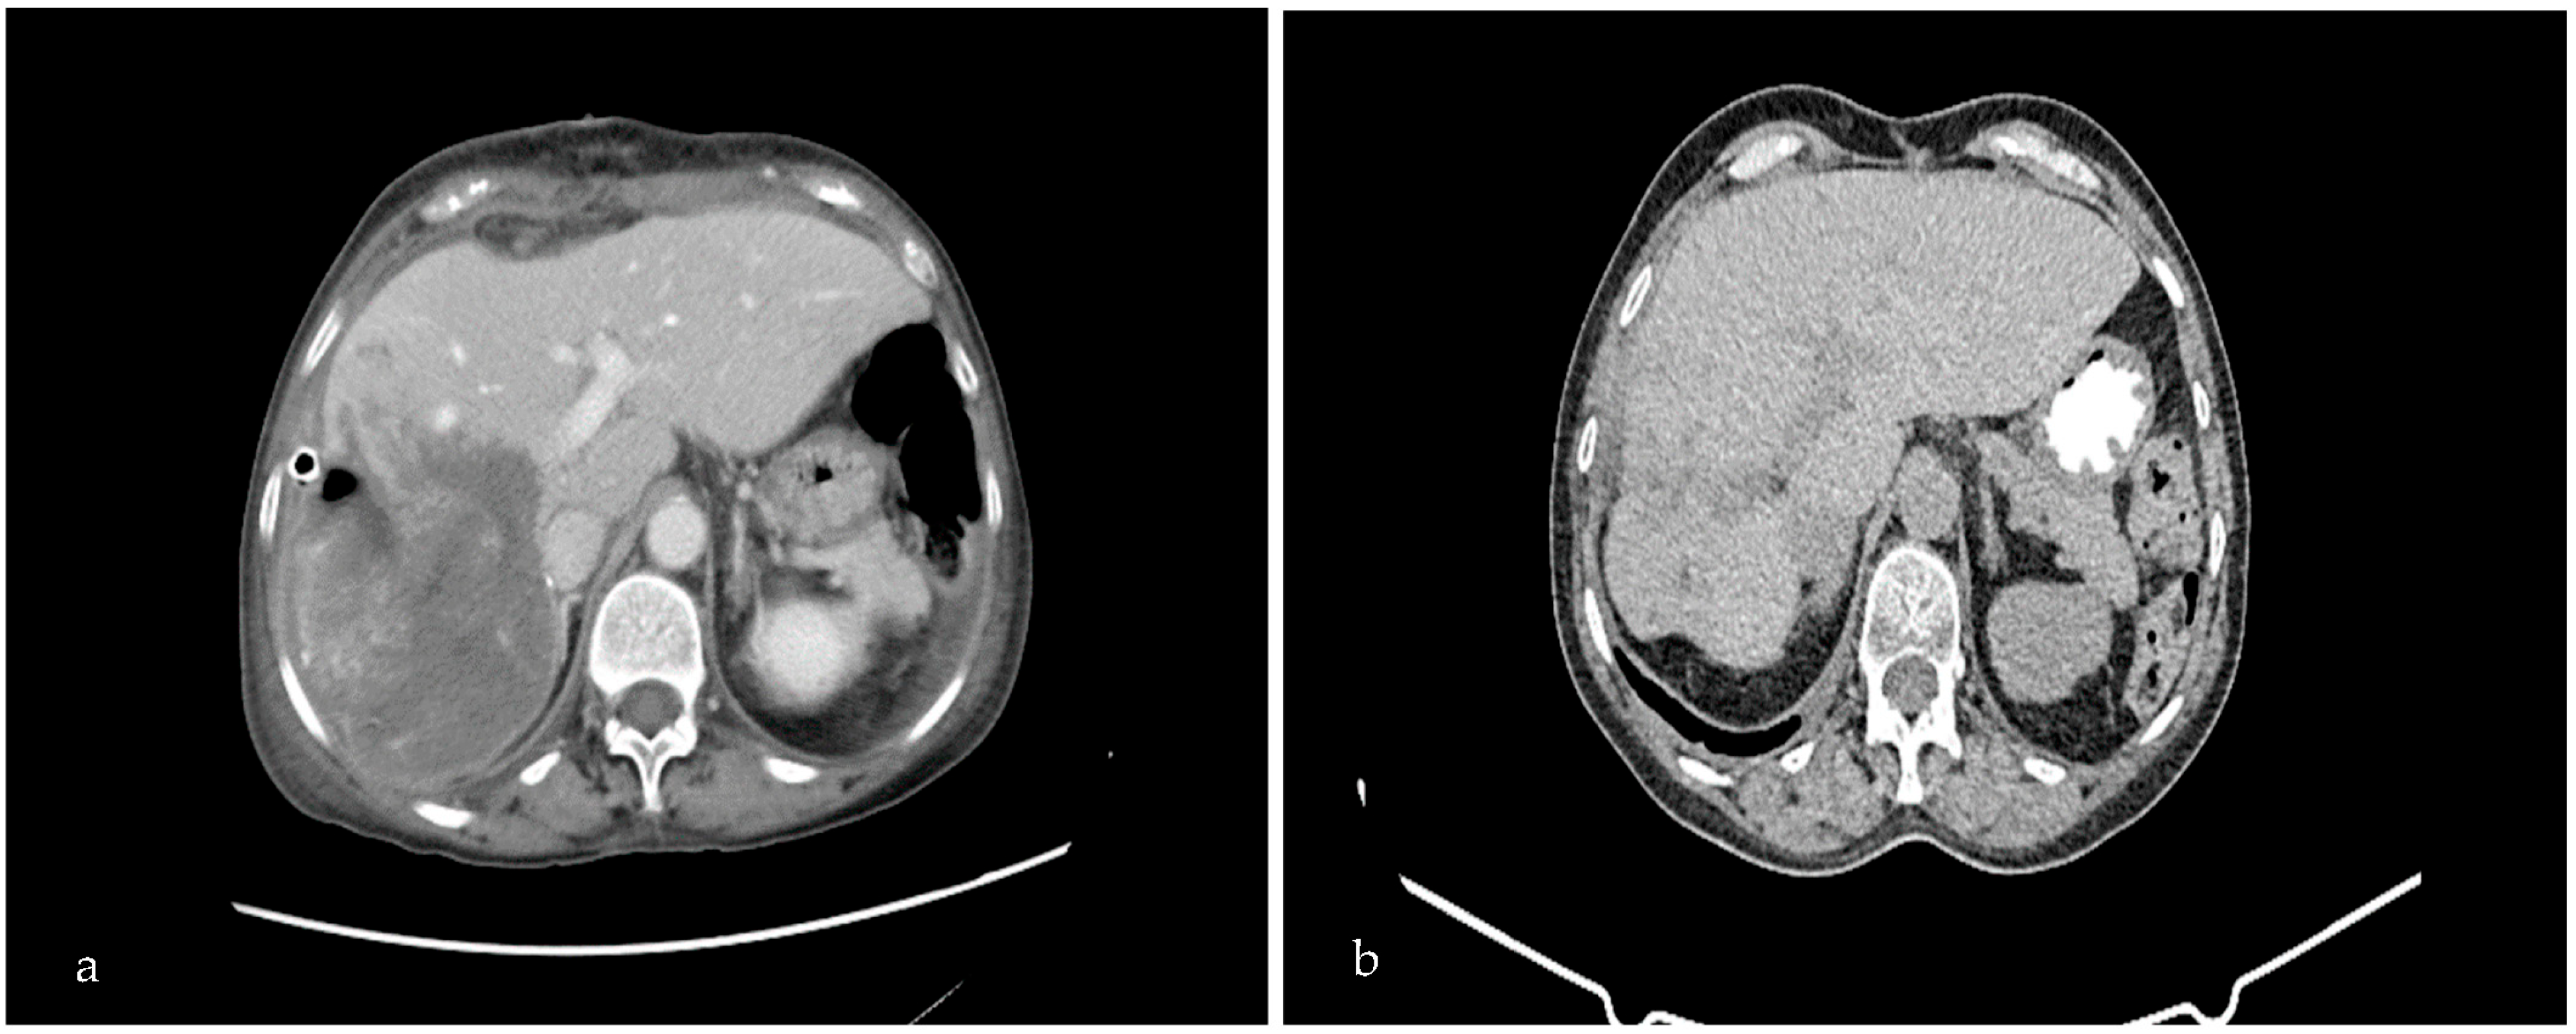

We proceeded to an extensive review of a 76-year-old patient who was admitted to our hospital center, presenting with right upper quadrant pain, which had initially appeared 3 months before, accompanied by fever (38–39 °C) and weight loss of 30 kgs in a period of 9 months and a sense of fullness. The patient complained of weakness, which hindered her daily activities. At the time of presentation, there was no sign of jaundice. Consequently, she underwent a CT scan and MRI, which demonstrated an oval transversal lesion measuring 17 × 14 × 11 cm (hydatid cyst) (Figure 1a) and occupying the right hepatic lobe. Furthermore, MRI imaging illustrated the dilation of the bile duct towards the IV and VI sectors of the liver. The MRI showed no pulmonary parenchyma involvement and a lack of enlarged lymph nodes. Laboratory tests revealed anemia (Hb: 10 mg/dL) and an increased white blood cell count (WBC: 16,000 K/μL), of which 87% were neutrophils. Elisa testing for Echinococcus was positive. Upon further inquiry, the patient revealed that she lived in a rural area and she was in close contact with sheep and dogs. Thus, according to the former data and based on the WHO criteria (daughter cyst in the solid matrix, Ce3b, WHO stage), we opted for a partial pericystectomy (removal of the endocyst and partially of the pericyst), which exhibits low morbidity and mortality rates when performed by an experienced surgeon.

Furthermore, the patient underwent post-operative treatment with 6 cycles of albendazole. Albendazole chemotherapy was found to be the primary pharmacological treatment to consider in the medical management of cystic echinococcosis and is, in general, used for reducing cysts, decreasing infection, and avoiding relapses. A follow-up CT scan of the patient 8 months post-operatively revealed deterioration of the remaining cavity of the suppurated hydatid cyst (Figure 1b).

Figure 1. Pre-operative (a) and post-operative (b) abdominal CT scan. Pre-operative CT demonstrates the suppurated echinococcal cyst in segments V, VI, VII, and VIII of the right liver lobe, with d: 17 × 14 × 11 cm. Eight-month post-operative CT scan shows deterioration of the remaining cavity of the suppurated hydatid cyst.